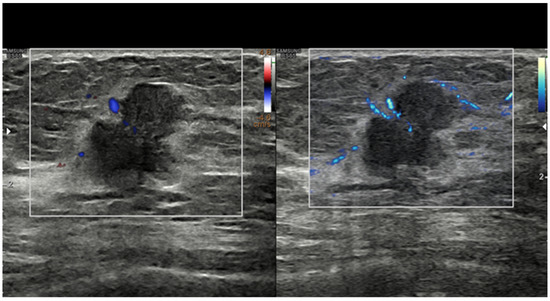

The transmission frequencies employed to scan breasts have increased through the years, moving from 7.5 MHz initially to 10–12 MHz and currently to 13–18 MHz. High-frequency transducers provide increased axial and soft tissue resolution, permitting improved differentiation of subtle shades of gray, margin resolution, and lesion conspicuity in the background of normal breast parenchyma [11]. Current transducers have a broad band of frequencies, allowing the operator to choose the most appropriate one in relation to the size of the given breast and based on the depth of the area of interest within it. However, most US companies now sell probes reaching frequencies up to 22–24 MHz. These transducers have been developed to study the skin, but there are a number of circumstances where they can be adopted to investigate the breast. These include skin abnormalities of the breast and axilla, nipple–areolar complex abnormalities, very small-size breasts, superficial areas in any size breasts, prepuberal breasts, male breasts, breast parenchyma abnormalities in subjects with implants, post-mastectomy chest wall, and intraoperative breast sonography [32] (Figure 2).

Figure 2. Breast intraductal papilloma. Detailed morpho-structural assessment working with a high-frequency transducer (22 MHz). Power Doppler detection of tumor vessels.